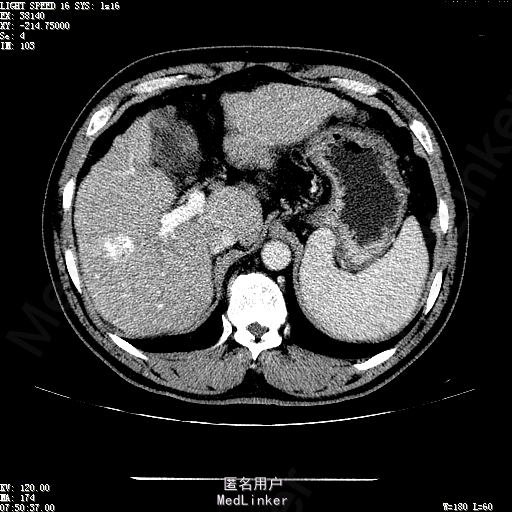

主诉:肝癌TACE治疗后36天 病史:患者两年前体检发现丙型肝炎病毒标志物阳性,于当地医院就诊诊断为"丙肝肝硬化",口服药物治疗,具体用药不详。定期复查肝功及肝脏影像学检查,2月前于医大二院行肝脏增强磁共振检查发现肝S6段动脉期增强结节,36天前在我院行DSA肝动脉造影明确"原发性肝癌"诊断并行"TACE"治疗,术后恢复良好,现患者为进一步行肝癌局部消融治疗来诊。

诊断:1、丙肝肝硬化 代偿期;2、原发性肝癌 S5段、S6段 该患诊断明确,既往曾行TACE治疗肝癌,S5段、S6段近右肾上极2处碘油沉积明确,S5段者较大,约2.31cm。超声显示清晰,为防止癌灶复发,适合行射频消融治疗。